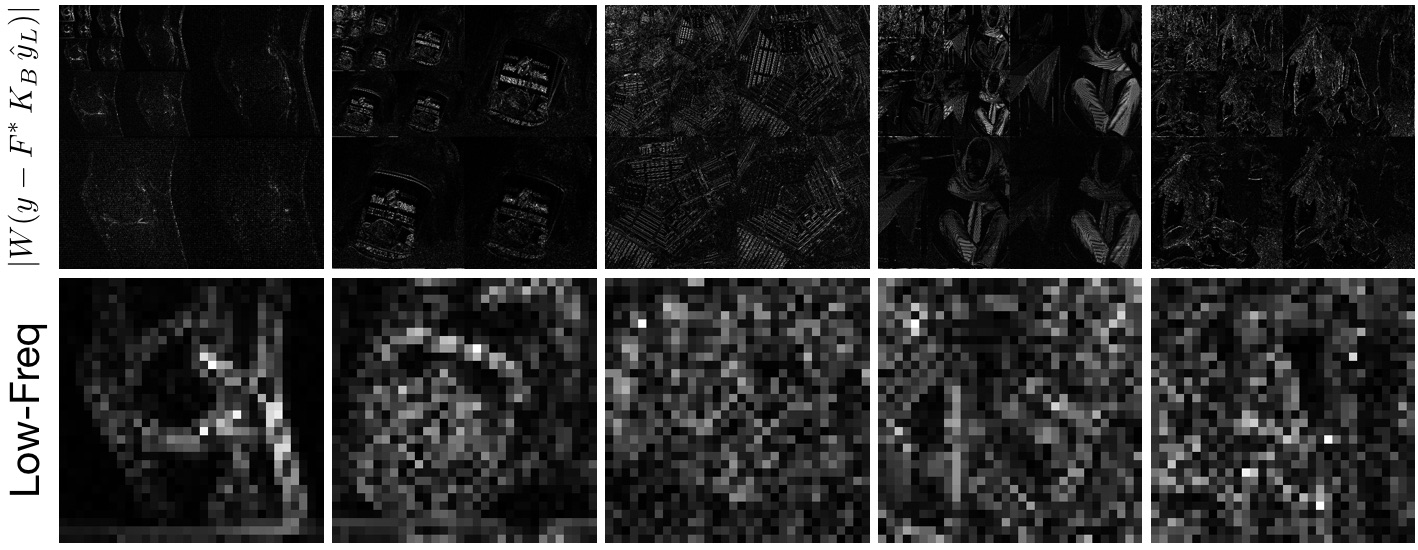

The key insight is that z=W(yy^L)𝑧𝑊𝑦subscript^𝑦𝐿z=W\,(y-\hat{y}_{L}) will be more sparse (have more values approximately equal to 00) than x𝑥x for the reasons presented in section 2. Figure 3 shows z𝑧z for the images of Fig. 2. Indeed, they are now better approximated by a sparse representation.

Refer to caption

Figure 3: Wavelet transforms of images after subtracting the low-frequency reconstruction from the image. (Top) Wavelet transform with r=4𝑟4r=4. (Bottom) lowest-frequency bin of the Wavelet transform. The lowest-frequency bin has many more values approximately equal to 00 than those of Fig. 2.